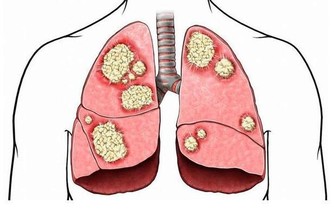

相信大家都不想痛風發作,不僅是因為那滋味太痛苦了,還因為它會帶來各種並發症,比如說關節疼痛,嚴重的甚至會變形,不能正常活動關節。若是尿酸結晶沉積在腎小管裡,還有可能損傷腎臟,形成結石,給身體加上另一重痛苦。